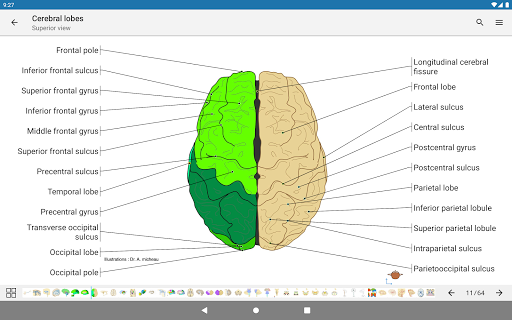

e-Anatomy memiliki lebih dari 26.000 gambar yang berisi serangkaian gambar dalam tampilan aksial, koronal, dan sagital serta radiografi, angiografi, gambar diseksi, bagan anatomi, dan ilustrasi. Semua gambar medis diberi label dengan cermat, lebih dari 967.000 label tersedia dalam 12 bahasa termasuk Terminologia Anatomica Latin.

- Gulir set gambar dengan menyeret jari Anda

- Perbesar dan perkecil

- Ketuk label untuk menampilkan struktur anatomi

- Pilih label anatomi berdasarkan kategori